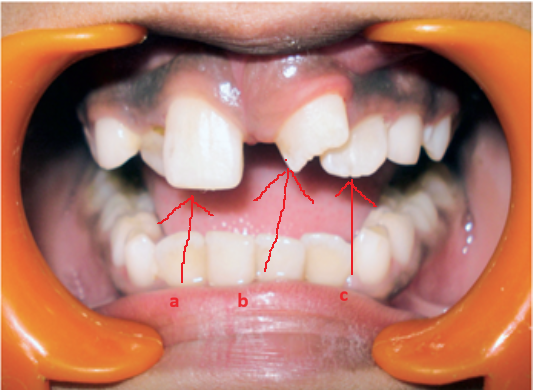

Răng thừa làm cho R21 mọc thưa và lệch về phía môi Răng thừa (a) làm R11 (b) bị kẹt không mọc ra được

Hình 2: Một số biến chứng của răng thừa